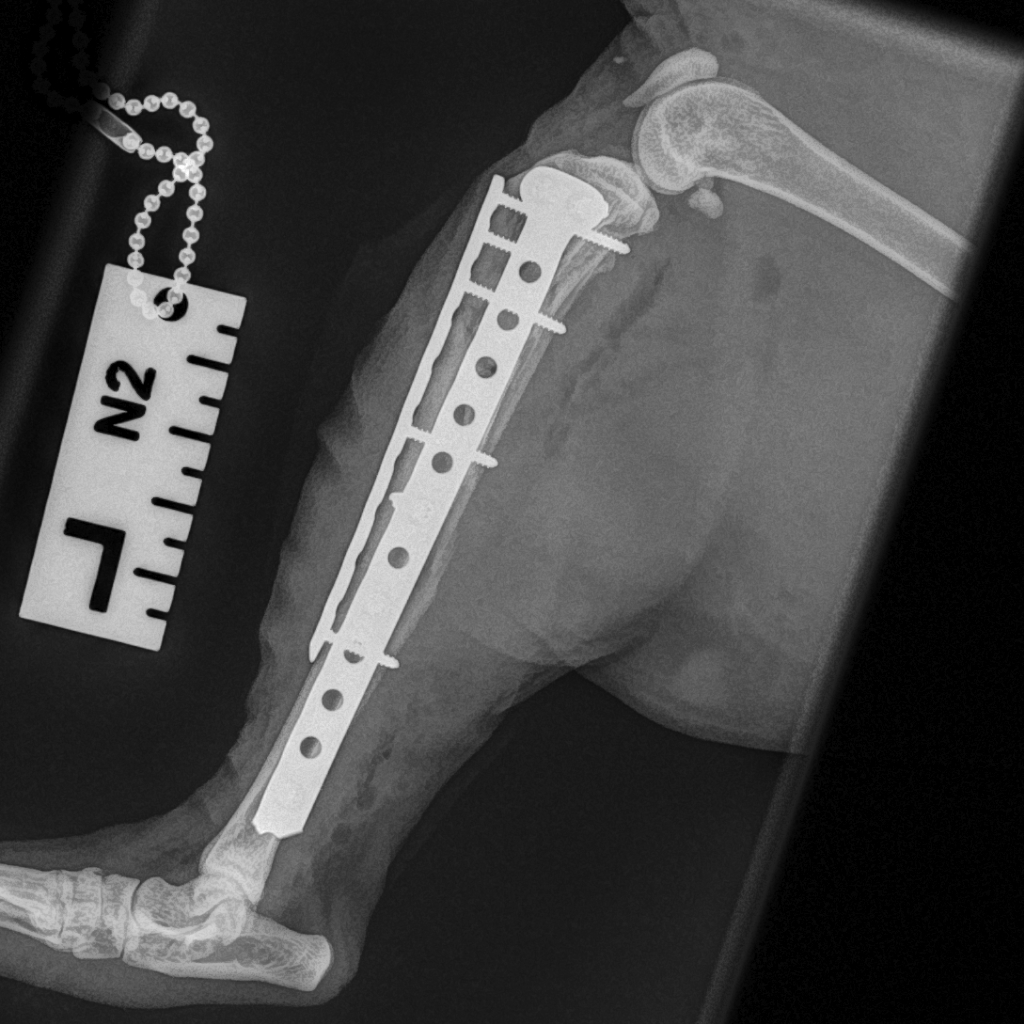

The Feline Lateral Ilial Plate (FLIP) was also designed by Ben Walton in collaboration with Fusion Implants.

Fractures of the ilium are very common in cats following road traffic accidents and, as part of the load-bearing axis, the ilium is an important bone for transfer of load from the spine to the pelvic limb.

The ilium is quite thin and so the multiple locking screws of the FLIP provide the surgeon with flexibility and the advantage of a pre-contoured implant.